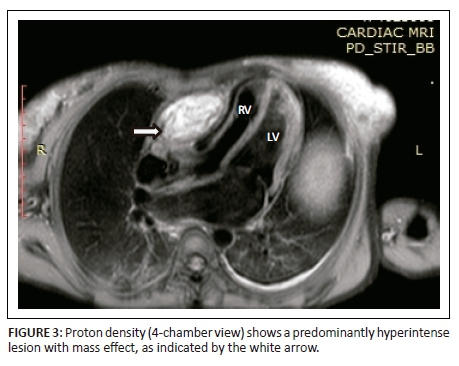

Magnetic resonance imaging was performed on a Philips Multiva 1.5 Tesla scanner. Images were acquired in the para septal long axis, short axis and four-chamber views. Intravenous contrast was administered to further evaluate the mass lesion. The findings confirmed a large 6 cm × 4 cm × 8 cm mass compressing the right ventricle. The short axis post contrast T1 spectral presaturation inversion recovery black blood (T1_SPIR_BB) sequence image in Figure 1 showed a high signal intensity mass lesion compressing the right ventricle; this was associated with a nodular pericardium and massive ascites. The lesion was closely adherent to the pericardium but separable from the RV wall. The mass remained hyperintense on T2 short tau inversion recovery black blood (T2_STIR_BB) sequences (Figure 2). Proton density short tau inversion recovery black blood (PD STIR BB) series in Figure 3 also demonstrated a predominantly high signal intensity mass with hypointense streaks. The persistent high signal on both T1 and T2 sequences indicated the absence of fluid. Failure to suppress on all the fat suppression sequences, confirmed the absence of fat. There was marked mass effect, which impeded ventricular filling in diastole. A pronounced septal bounce was evident on the functional imaging series (not shown). The cardiac function was severely depressed with an ejection fraction (EF) of < 40%.